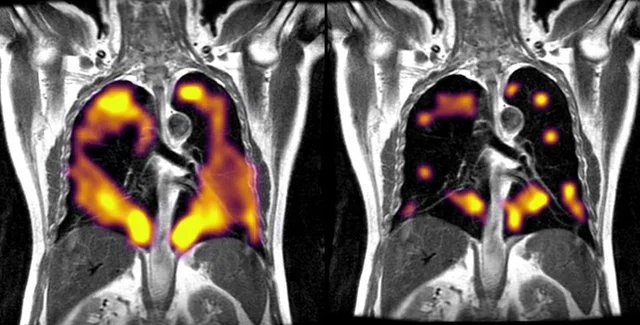

Во время сканирования пациент вдыхает ксенон, что позволяет увидеть структуру и вентиляцию легких | Фото: University of Oxford Department of Oncology

Медики использовали новый вид технологии визуализации, называемый "МРТ с гиперполяризованным ксеноном" (129Xe МРТ). Технология дает возможность получить очень подробные сведения о работе легких и передаче кислорода в кровь.

"МРТ 129Xe выявляет те части легких, где физиология поглощения кислорода нарушена из-за длительного воздействия COVID-19 на легкие", — говорит Джим Уайлд, руководитель отдела визуализации в Университете Шеффилда, Великобритания.

В исследовании принимали участие девять пациентов, которые выписались из больницы около шести месяцев назад. У них была постоянная одышка, несмотря на то, что результаты КТ нарушений не показали.

"Наше сканирование с использованием МРТ с гиперполяризованным ксеноном показало, что аномалии, которые обычно не видны при привычных сканированиях, действительно присутствуют, и эти аномалии препятствуют попаданию кислорода в кровь, как это должно происходить во всех частях легких", — говорит радиолог Фергус Глисон, участник исследовательской группы.

Революционная методика визуализации показывает одни из первых эмпирических признаков повреждения легких у пациентов, перенесших COVID, подтверждая, что это не просто ипохондрическое состояние. Ученые теперь имеют новый вид мониторинга повреждения легких, а будущие исследования должны показать, как долго может длиться повреждение, и можно ли его вылечить.